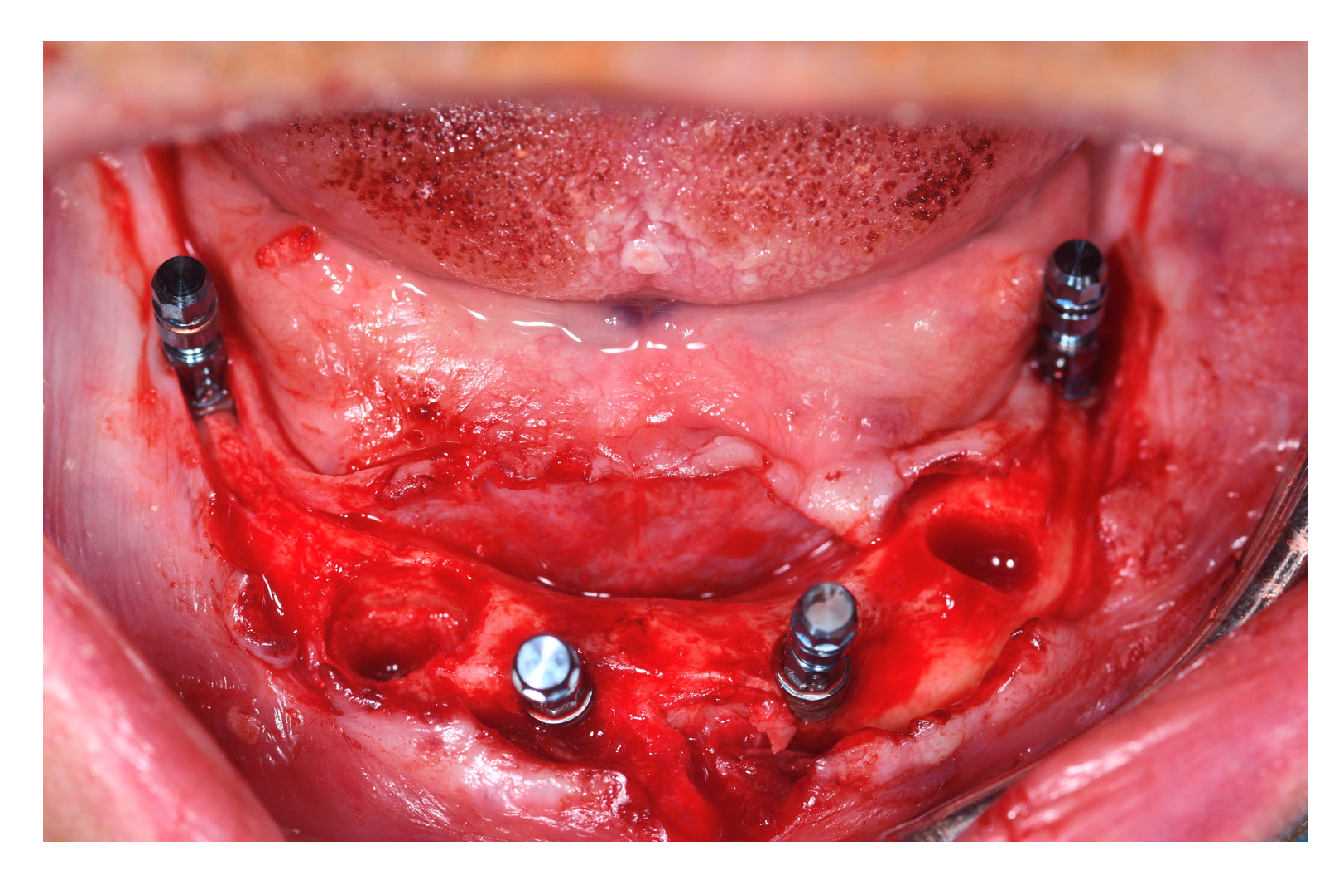

Intraoral picture of implant placement.

Implant sites for participants belonging to T1 and C were undersized, if needed, in order to reach the maximum primary stability by drilling bone, skipping the last dedicated drill in soft bone class 4. Implant placement followed the Columbus Bridge Protocol described in 2011 by Tealdo T. et al. [12]. The two distal implants were mesio-distally tilted and had a minimum length of 12 mm (Figure 4).

After implant placement, the multi-unit abutments were connected to the implants at 25 Ncm according to the following pattern:

- 0° or 17° on the anterior implants;

- 30° on the posterior tilted implant (Figure 5).

Figure 5. Abutment connection.